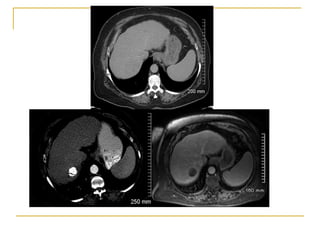

80 patients with HCC 3- 8cm (mFUP 32m)

CP A and B

< UNOS T4

23 with recurrent disease

Lesion size

52 - 3-5 cm

28 - 5-8 cm

Results

Complete ablation – 87.5%

94% cw 75% depending on size

22% local recurrence

15% vs 41% depending on size

Location near bile duct

54% distant recurrence

More frequent in recurrent HCC

Complications – 7.5% without mortality

1 tract seeding

Role for microwave in larger lesions

Survival 1 2 3 5 years 81% 68% 56% 34%